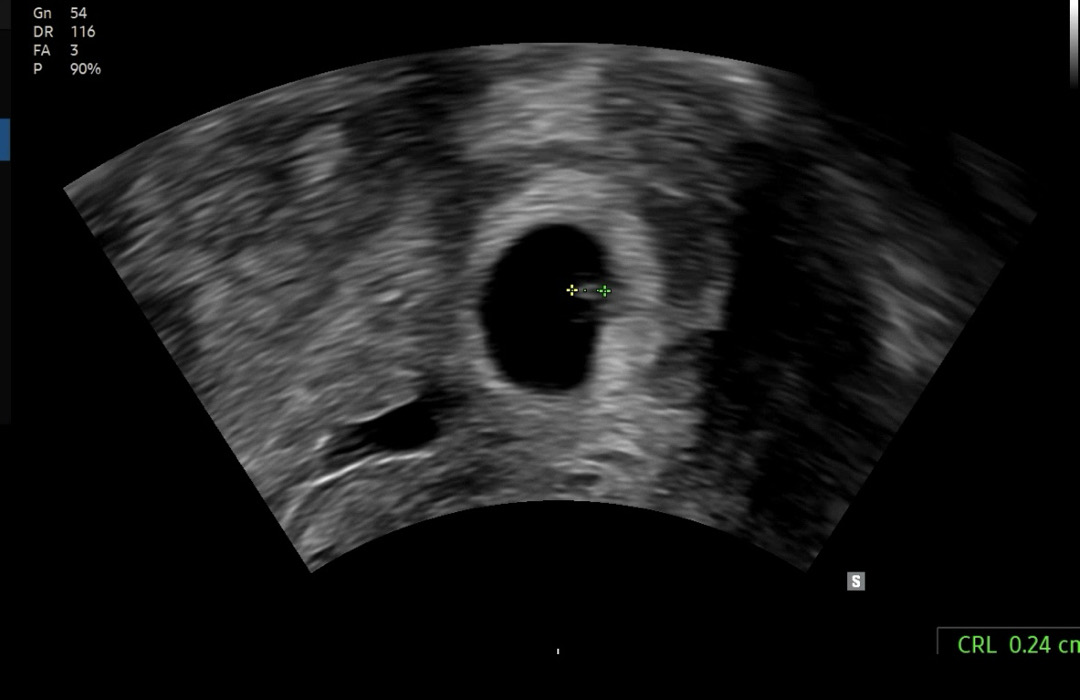

5/11 막생, 5주5일차 첫 초음파 보고왔어요

원포 테스트기 역전 안되길래 불안했는데 난황, 0.24cm 아가도 보고왔어요ㅎㅎ 심장 뛰는 것도 보였는데 아직 너무 작아서 소리는 안들렸어요. 저렇게 작은 생명이 뱃속에 있다고 생각하니까 너무 신기하면서도 요새 속도 울렁거리고, 입맛도 없고, 소화도 안 되고, 체력도 딸리는데 쪼꼬만 아기가 이런 큰 영향이 있다는 게 어이가 없었어요..ㅎㅎㅎ 혹시 저처럼 입맛없는 산모분들 뭐 드시나요..? 메뉴 추천해주세요🥹